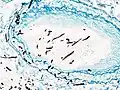

| Pulmonary invasive aspergillosis in a person with interstitial pneumonia (autopsy material), using Grocott's methenamine silver stain | |

On microscopy, Aspergillus species are reliably demonstrated by silver stains, e.g., Gridley stain or Gomori methenamine-silver.[27] These give the fungal walls a gray-black colour. The hyphae of Aspergillus species range in diameter from 2.5 to 4.5 μm. They have septate hyphae,[28] but these are not always apparent, and in such cases they may be mistaken for Zygomycota.[27] Aspergillus hyphae tend to have dichotomous branching that is progressive and primarily at acute angles of around 45°.[27]